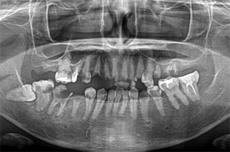

オールオン4の治療例:1

治療前

治療後

オールオン4の治療例:2